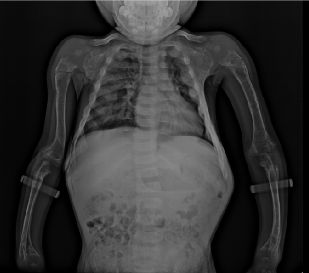

鸡胸(pectus carinatum)又称鸽胸。胸骨向前隆起畸形,状如鸡、鸽子之胸脯故称之为鸡胸,是前胸壁第二种常见的胸廓畸形,较漏斗胸少见,发病率约千分之一,男女比例约4:1,占所有胸壁畸形的16.7%。病因尚未明确,可能与遗传有关,有家族史者约20%~25%。一般认为是肋骨和肋软骨过度生长造成的,胸骨的畸形是继发于肋骨畸形的,也可继发于胸腔内疾病。。

王长江说,实际上,仅通过补钙并不能治疗鸡胸,这是一种误区。鸡胸是一种常见的胸廓畸形,表现为:胸骨向外异常突出,状如禽类的胸骨,也是“鸡胸”的由来。它和漏斗胸一样,属于常见的胸廓畸形。以往认为鸡胸发病多与钙磷代谢有关,多由营养不良引起钙的摄入不足或吸收障碍引起,因此很多人采取补钙治疗。但近些年研究发现,鸡胸的主要原因是肋骨和肋软骨过度生长造成的,变长的肋软骨向前凸起形成鸡胸,向后凹陷形成漏斗胸,必须通过微创手术才能有效矫正鸡胸病。